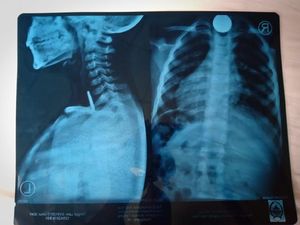

Tim dokter dikejutkan dengan kasus seekor gurita yang menyangkut di kerongkongan pasien. Pasien mengalami sulit menelan dan muntah usai makan gurita.